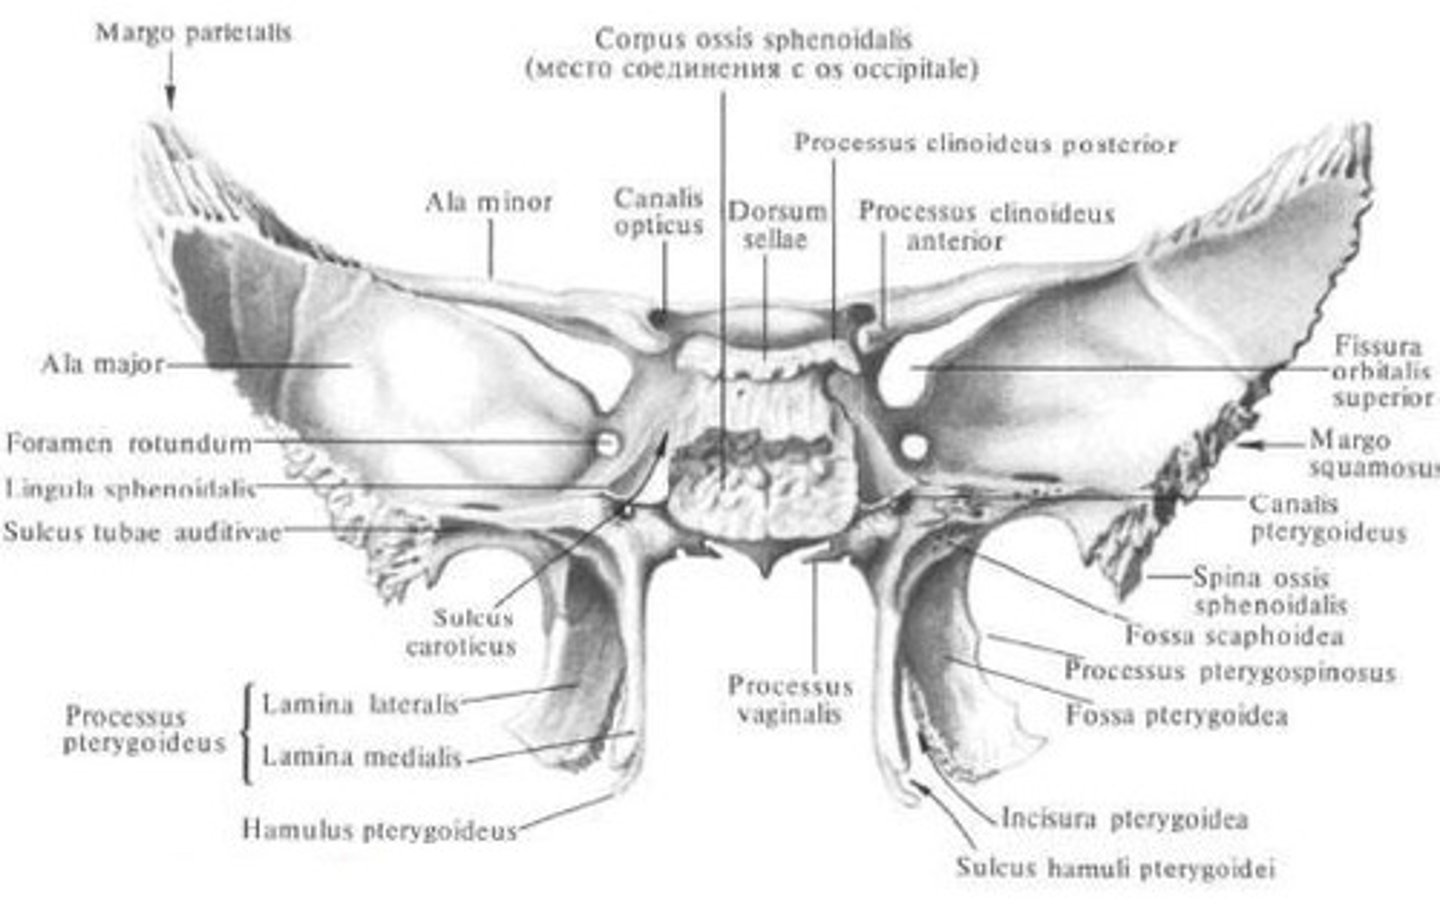

os sphenoidale

pleištakaulis

fossa hypophysialis

posmegeninės liaukos duobė

mašasis ir didysis sparnai

canalis opticus

reginis kanalas

processus pterygoidei

Sparninės ataugos

corpus

Pleištakaulio kūnas

Sinus sphenoidalis

pleištakaulio antis

ala major

Didysis sparnas

ala minor

mažasis sparnas